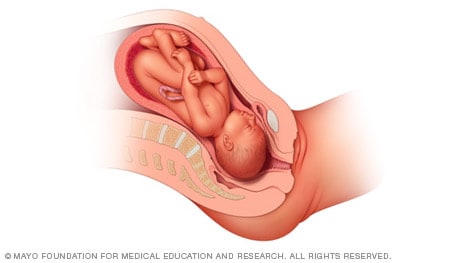

Complete and incomplete breech

A complete breech presentation, as shown below, is when the baby has both knees bent and both legs pulled close to the body. In an incomplete breech, one or both of the legs are not pulled close to the body, and one or both of the feet or knees are below the baby’s buttocks. If a baby is in either of these positions, you might feel kicking in the lower part of your belly.

If you are more than 36 weeks into your pregnancy and your baby is in a complete or incomplete breech presentation, your health care professional may try to move the baby into a head-down position. This is done using a procedure called external cephalic version. It involves one or two members of the health care team putting pressure on your belly with their hands to get the baby to roll into a head-down position.

If the procedure isn’t successful, or if the baby moves back into a breech position, talk with a member of your health care team about the choices you have for delivery. Many babies in a complete or incomplete breech position are born by planned C-section.